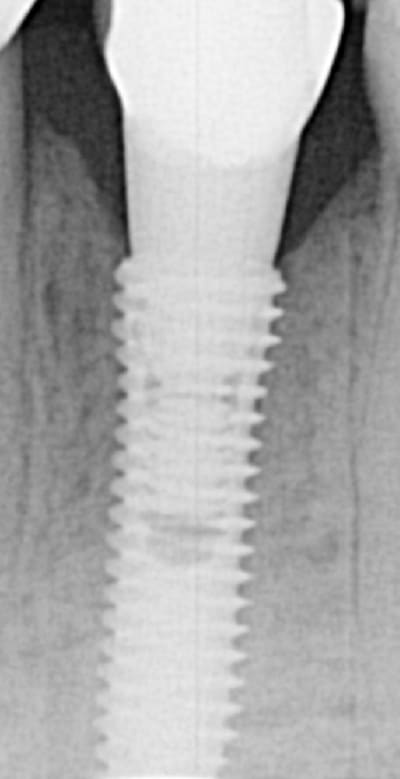

EII et Mise en vitrine immédiate, ici implant très enfoui, premier cliché à 3 mois post-op puis à un an (il faut préciser que le contrôle de plaque est plus que parfaitement réalisé par le patient).

(implant Dentium superline avec état de surface SLA)